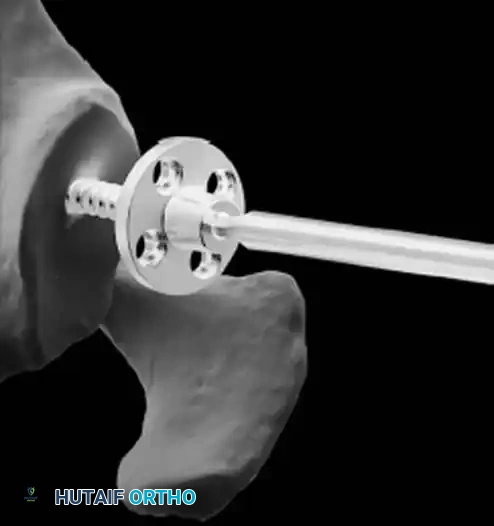

* Glenoid Baseplate: Must be positioned inferiorly on the glenoid to avoid scapular notching. A slight inferior tilt (10 degrees) is often utilized.

* Glenosphere: Typically 36 mm or 42 mm. Larger spheres increase stability and range of motion but may increase the risk of notching.

* Humeral Stem: Often placed in 0 to 20 degrees of retroversion.